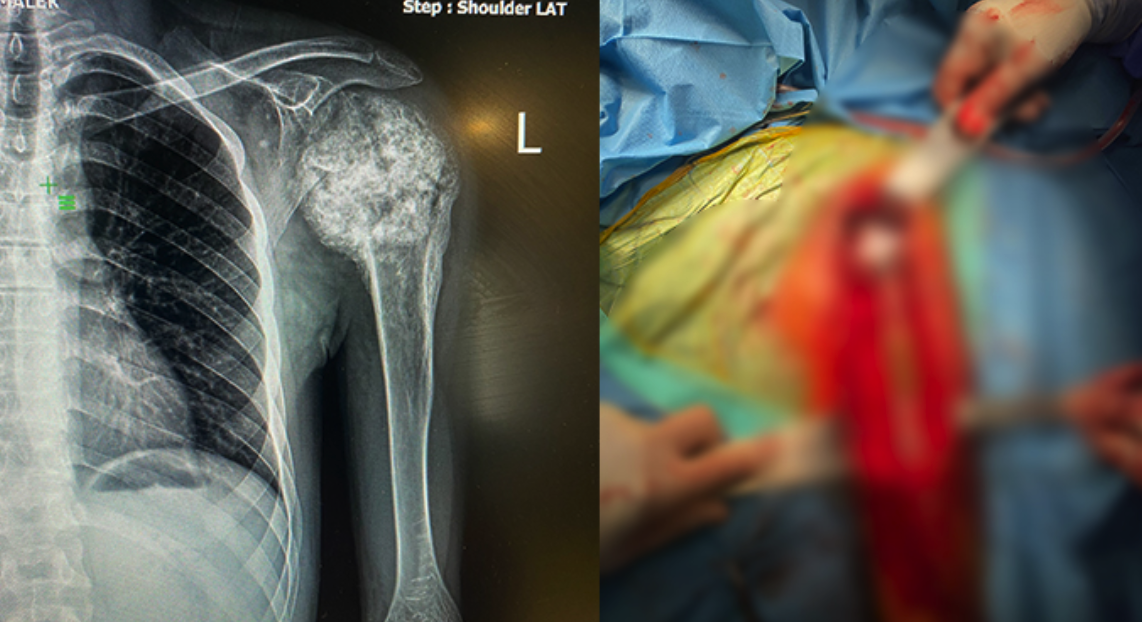

Memohaber.com'da yer alan haberde; 20 yaşındaki M.M. omzundaki şişlik ve hareket kısıtlılığı nedeniyle başvurduğu hastanede kemiğinde tümör olduğunu öğrendi. Çevresindekilerin de yardımıyla yaptığı araştırma sonucu Türkiye'nin 3. büyük şehir hastanesi konumundaki Gaziantep Şehir Hastanesi'nin Ortopedi ve Travmatoloji bölümüne başvurdu.

Hastanede görev yapan Ortopedi ve Travmatoloji uzmanı Op. Dr. İbrahim Halil Demir tarafından yapılan ameliyat 20 yaşındaki M. M.'ye umut oldu. Omuz kemiğinde kötü huylu tümörü bulunan genç hasta yapılan başarılı cerrahi ile tümörden kurtuldu. Omuz kemiğindeki tümörden kurtulan M.M., ameliyat edilen bölgeye takılan protezle şifa buldu.

Türkiyenin en önemli referans merkezlerinden biri olan Ankara Üniversitesi’nde “Kemik ve Yumuşak Doku Tümörleri” konusunda özel eğitim alan Op. Dr. İbrahim Halil Demir bu cerrahi işlemin Gaziantep’te ilk defa gerçekleştirildiğini aktararak “Milletimizin hizmetindeyiz.